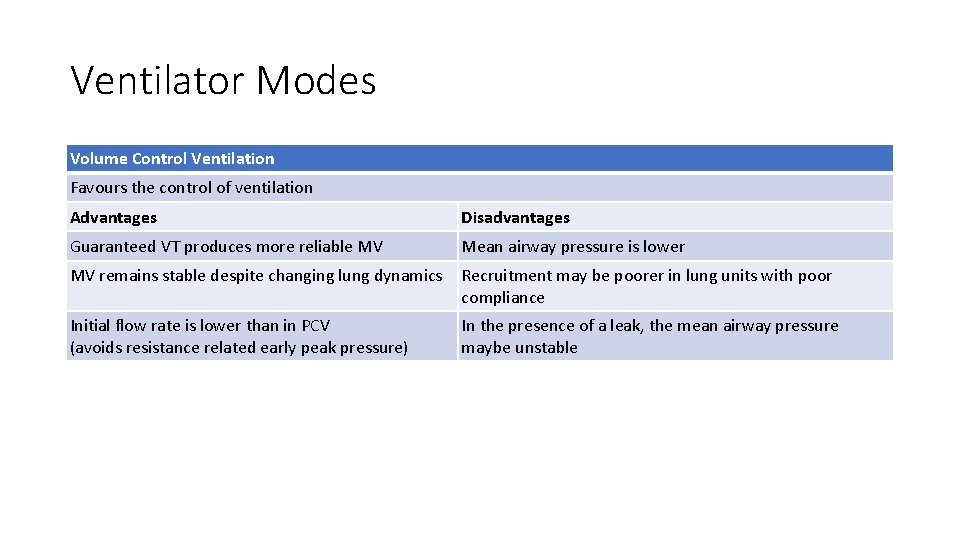

Ventilator Modes Volume Control Ventilation Favours the control of ventilation Advantages Disadvantages Guaranteed VT produces more reliable MV Mean airway pressure is lower MV remains stable despite changing lung dynamics Recruitment may be poorer in lung units with poor compliance Initial flow rate is lower than in PCV (avoids resistance related early peak pressure) In the presence of a leak, the mean airway pressure maybe unstable